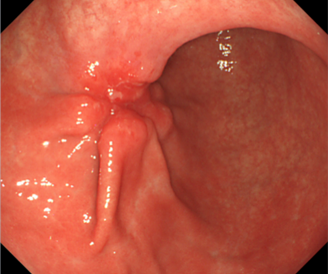

This slide show features a CT image, and pathology images of gastrointestinal stromal tumors (GISTs) arising in the stomach using H&E, CD34, and c-Kit staining.